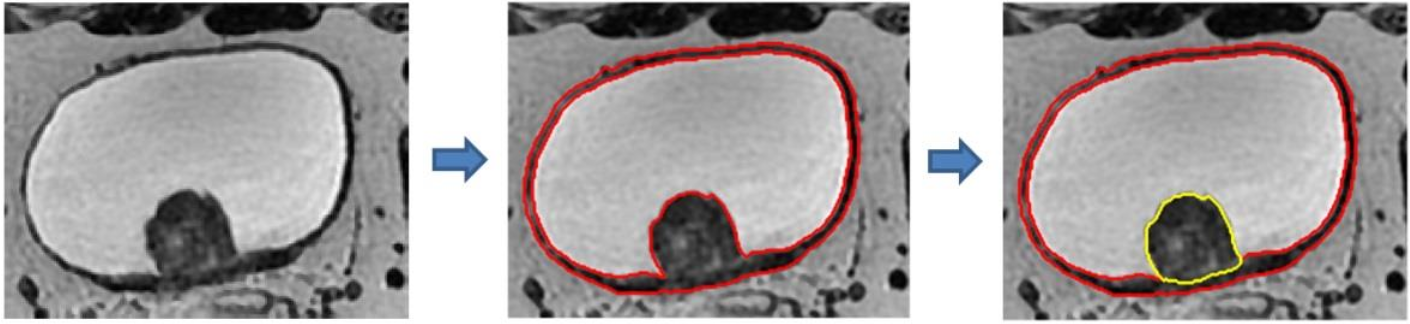

挑战赛是本届ISICDM会议的一个重要环节,吸引了来自境内外多所高校的队伍参加。此次膀胱癌图像分割挑战赛使用的是来自空军军医大学的真实膀胱癌临床数据,并且大赛不允许反复提交分割结果,避免了传统分割挑战赛中参赛者通过反复提交结果刷分数的弊端。此次挑战赛具有热身赛,排位赛和决赛三个阶段。其中排位赛和决赛环节的每场比赛时间越来越短,也越来越逼近真实临床环境。在决赛环节,参赛队伍现场展示图像的分割结果,评委和观众在台下实时观看参赛代表的软件操作过程,所得到的结论真实可信。